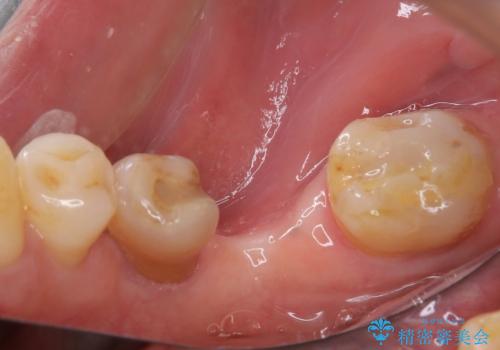

インプラント埋入時に植立具合の安定性を測定したところ、十分な数値が得られたため、速やかに仮歯を装着して咬合回復をさせることができました。

外科処置を1回に抑えることができ、あっという間に治療を終えることができました。